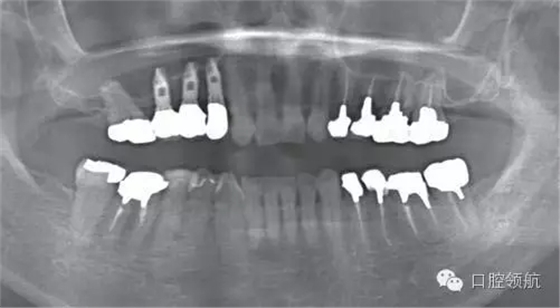

圖8 術后7年6個月的曲面斷層影像

圖9 治療結束后7年6個月的口內(nèi)正面像

圖10 治療結束后7年6個月的口內(nèi)腭側像